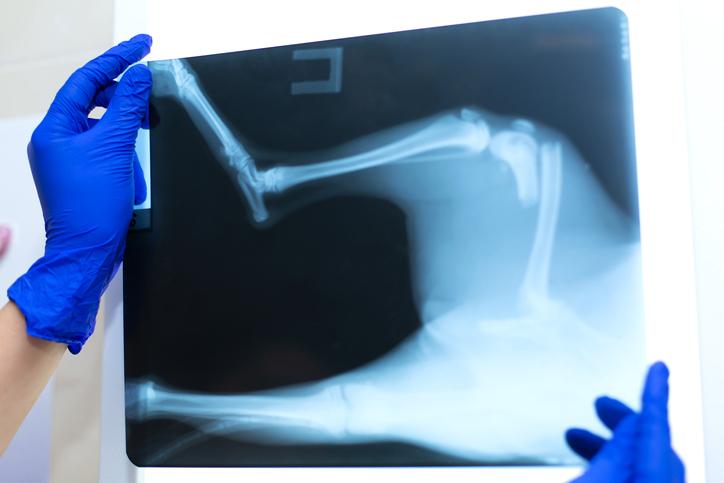

Se debe conocer que una fractura es algo distinto a una dislocación en perros, aunque afortunadamente los signos son prácticamente los mismos, y el diagnostico definitivo se realiza mediante rayos X por el médico veterinario.

Las fracturas a nivel de la escápula son poco frecuentes y son asociadas a traumatismos por atropellos. Las fracturas más frecuentes en miembros torácicos son a nivel de húmero y radio cúbito, que pueden lesionarse por infinidades de accidentes, desde arrollamientos hasta caídas.